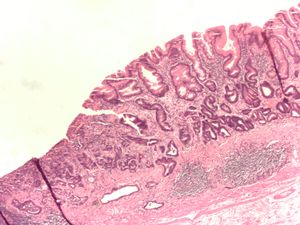

ـ التنطير الهضمي والخزعة: مع التطور الكبير في مجال صناعة المناظير الضوئية الليفية المرنة flexible fiberoptic endoscopes، صار من السهل إجراء فحص كامل ودقيق لمخاطية المعدة، ومشاهدة التغيرات المرضية، ومنها سرطان المعدة، مباشرة، وكذلك أخذ خزعات متعددة منها من أجل التشخيص النسيجي. ويجب أخذ 4 إلى 6 خزعات من أي آفة مشبوهة في المعدة لرفع دقة التشخيص.

Poor to moderately differentiated adenocarcinoma of the stomach. H&E stain.

Adenocarcinoma of the stomach and intestinal metaplasia. H&E stain.